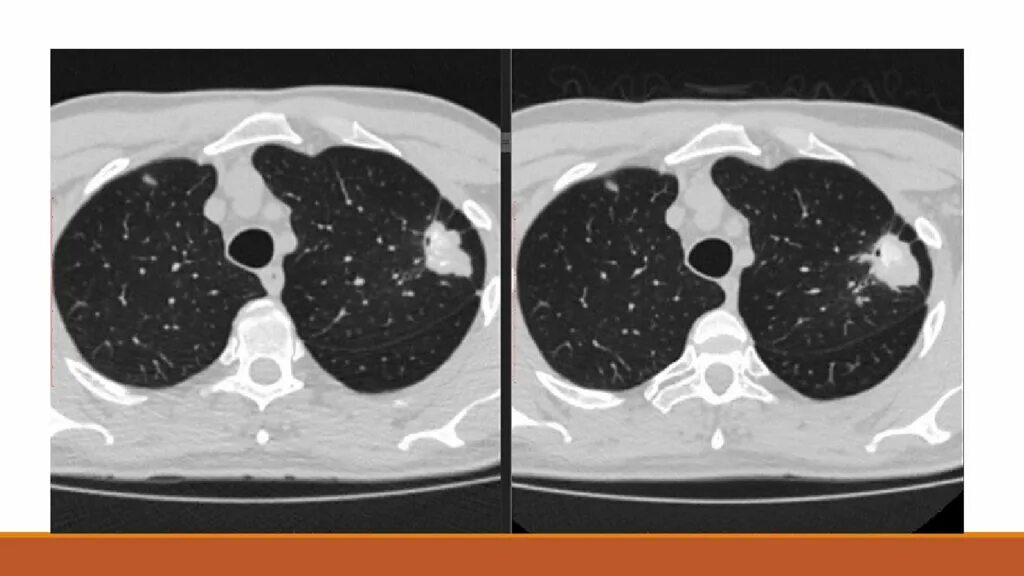

Кт после ковид